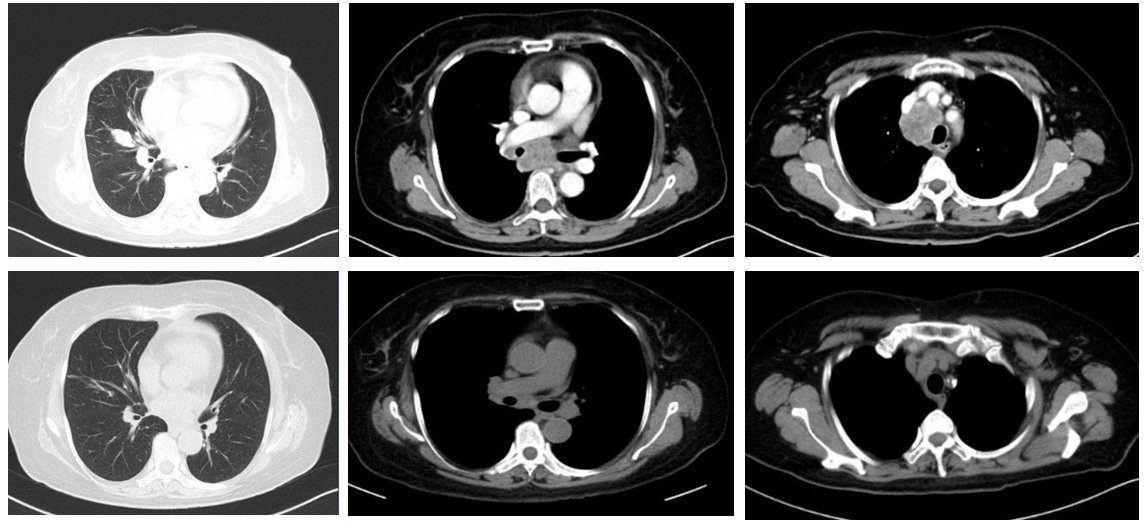

CT:符合右肺癌并右肺门、纵隔、右侧锁骨上淋巴结转移CT表现,较前好转;右肺中叶小叶间隔增厚,癌性淋巴管炎不能除外;双肺结节灶,部分消失,建议密切随诊复查;心包积液,较前较少;上腹部CT平扫未见明显异常(图2)。

图2. 化疗前后,CT变化